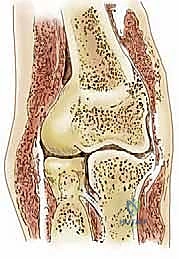

التهاب العظم والغضروف السالخ (OCD) هو حالة مرضية بؤرية تصيب العظم تحت الغضروفي (Subchondral Bone). تبدأ القصة عندما ينقطع الإمداد الدموي الدقيق عن جزء صغير من العظم الموجود مباشرة تحت الغضروف المفصلي في الرأس الصغير (Capitellum).

نتيجة لنقص التروية الدموية (Ischemia)، يموت هذا الجزء من العظم (Avascular Necrosis). وبما أن الغضروف المفصلي يعتمد جزئياً في تغذيته ودعمه الميكانيكي على العظم السليم تحته، فإن الغضروف يبدأ بالضعف والتشقق. مع استمرار الحركة والضغط، يمكن أن ينفصل هذا الجزء الميت من العظم والغضروف المغطي له كلياً أو جزئياً، ليسقط كجسم حر (Loose Body) داخل تجويف المفصل، مما يشبه "الحصاة داخل الحذاء"، مسبباً ألماً مبرحاً وتوقفاً مفاجئاً في حركة المرفق.

1. المرحلة الأولى (الآفة المستقرة): تليّن في الغضروف مع بقاء العظم في مكانه. الأشعة السينية قد تكون طبيعية، لكن الرنين المغناطيسي يكشف تورم العظم.

2. المرحلة الثانية (انفصال جزئي): يبدأ الغضروف بالتشقق، وتظهر حدود واضحة للقطعة المصابة في الأشعة، لكنها لا تزال ثابتة في مكانها.

3. المرحلة الثالثة (انفصال كامل بدون تحرك): القطعة العظمية الغضروفية منفصلة تماماً ولكنها لا تزال قابعة في حفرتها (Crater).

4. المرحلة الرابعة (الجسم الحر - Loose Body): تسبح القطعة بحرية داخل المفصل، تاركة تجويفاً فارغاً في الرأس الصغير.